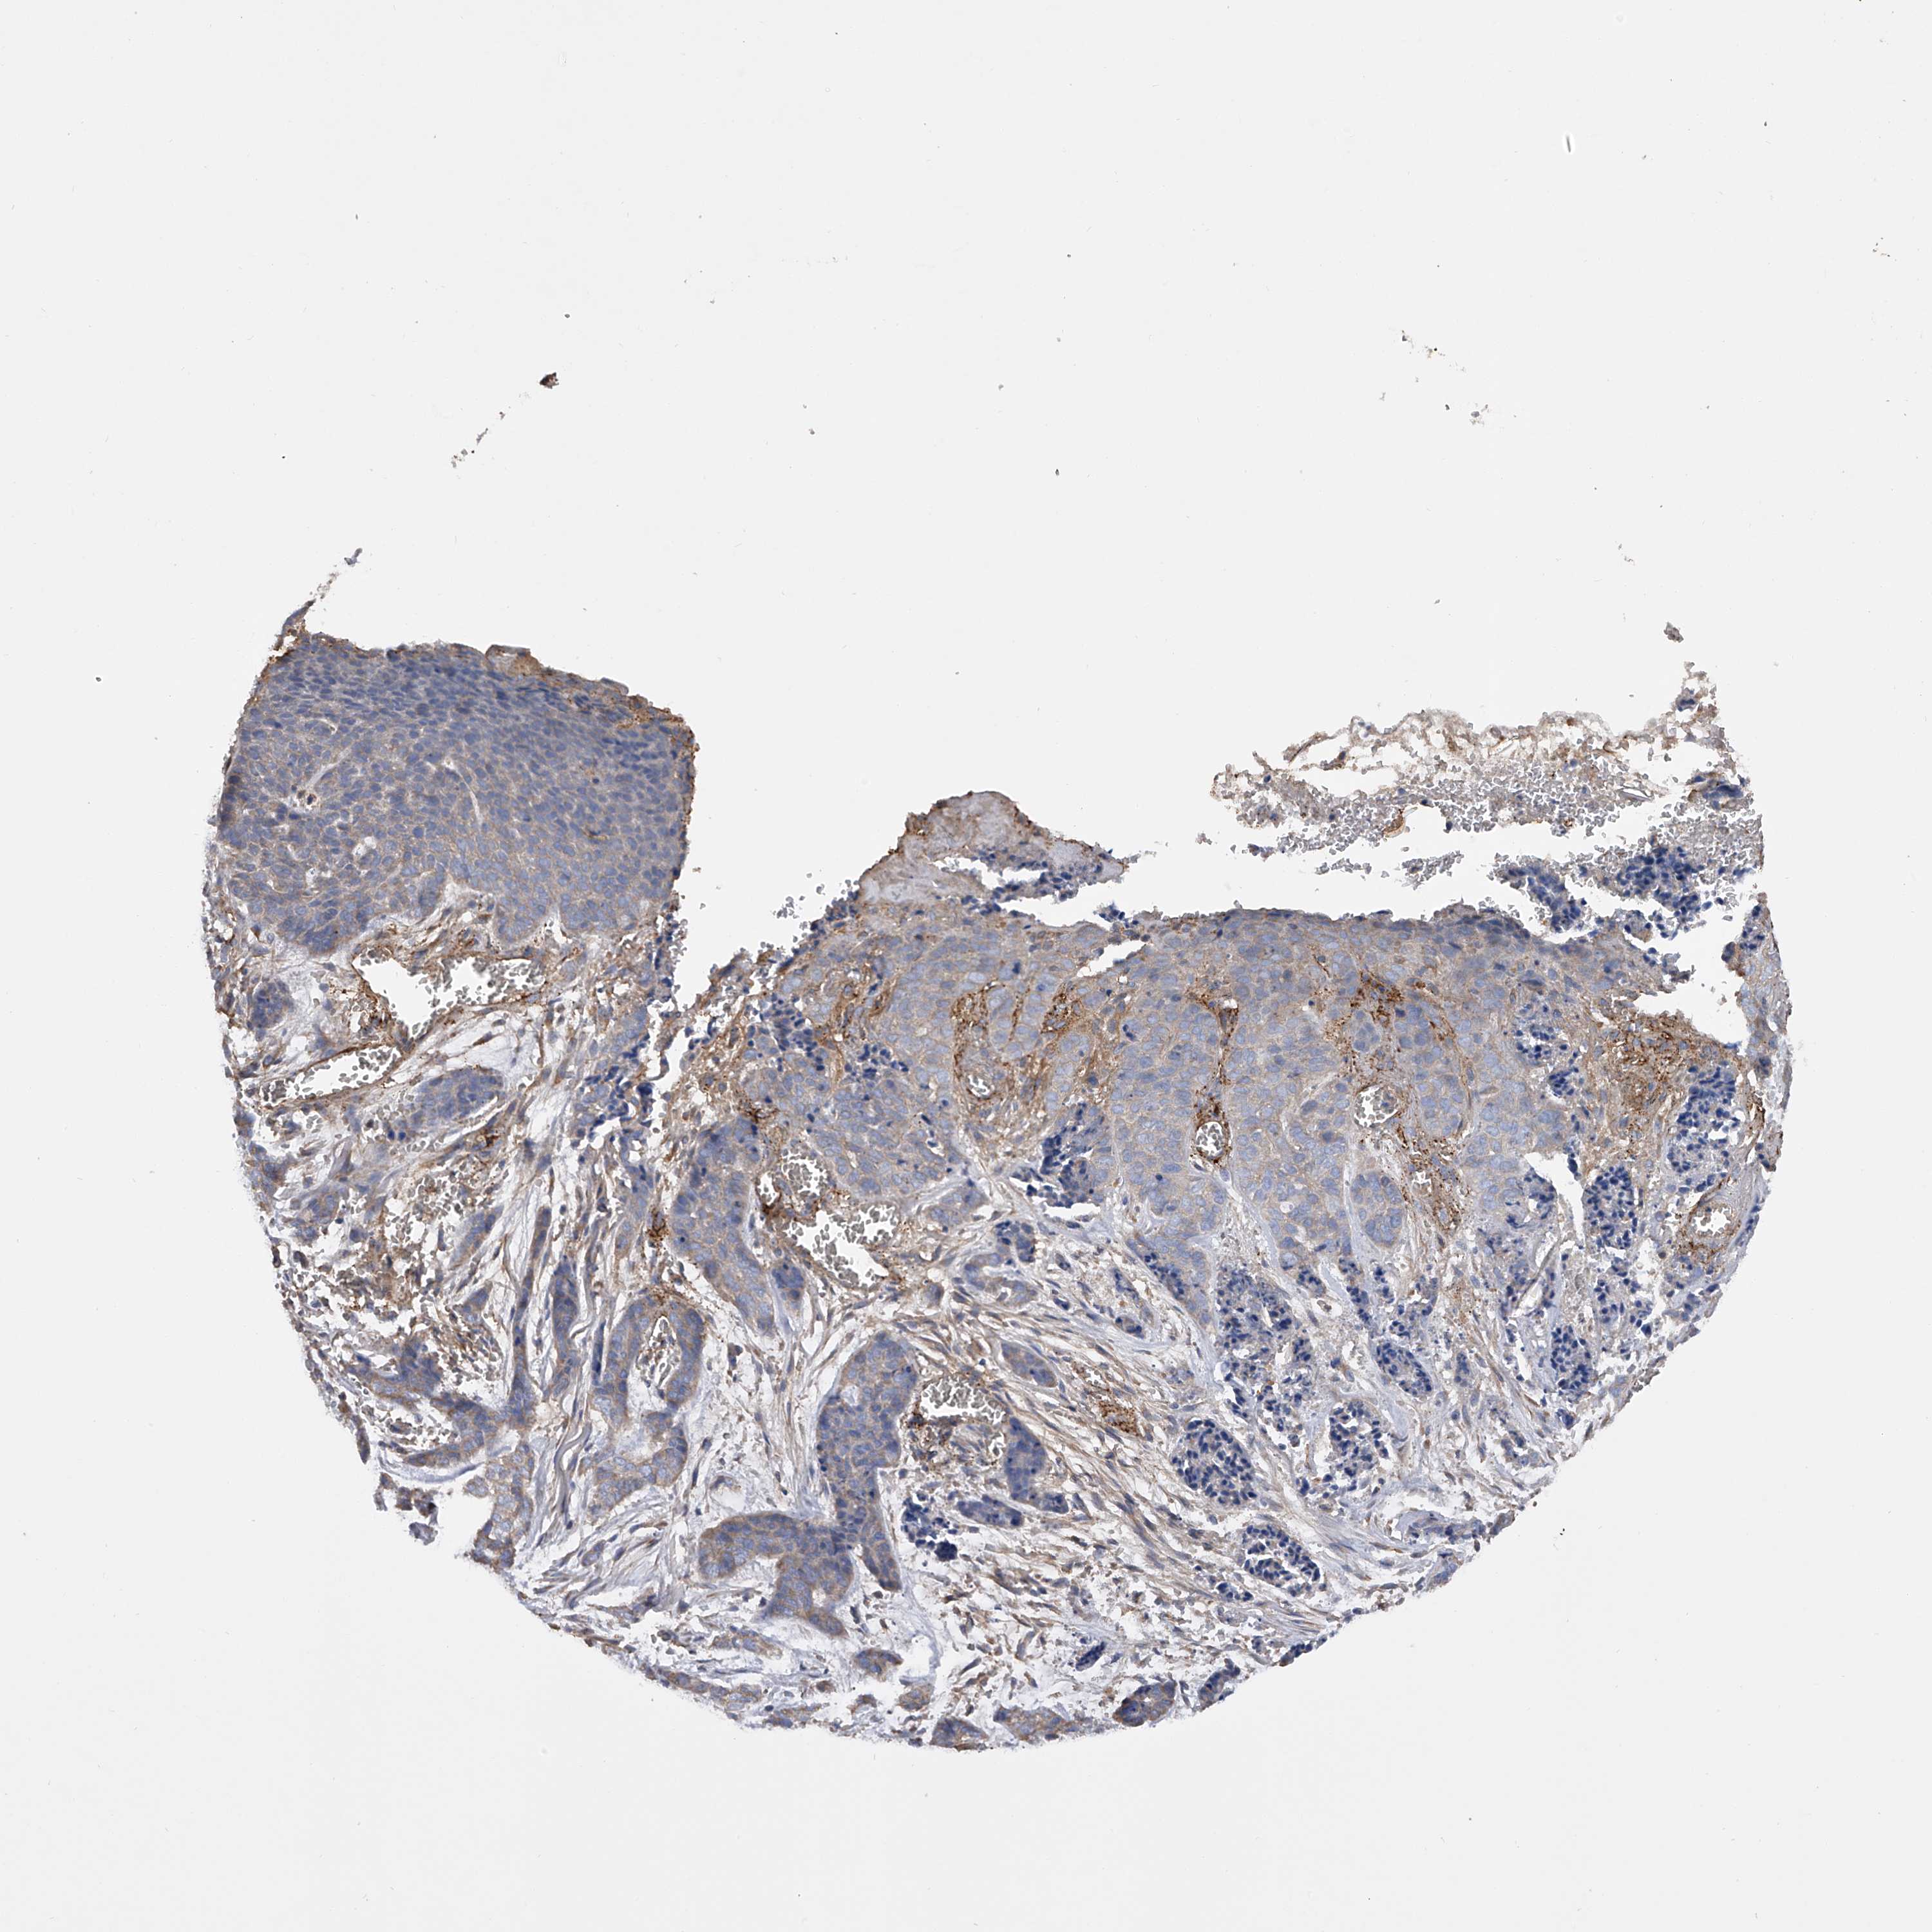

CANCER SKIN CANCER Show tissue menu

Basal cell and squamous cell cancer

SKIN CANCER - Protein expressioni

A mouse-over function shows sample information and annotation data. Click on an image to view it in a full screen mode. Samples can be filtered based on level of antibody staining by selecting one or several of the following categories: high, medium, low and not detected. The assay and annotation is described here.

Each image is clickable and will lead to virtual microscopy that enables deeper exploration of all samples and also displays staining intensity scores, fraction scores and subcellular localization as well as patient and tissue information for each sample.

Antibody HPA030106

Squamous cell carcinoma, NOS

Squamous cell carcinoma, metastatic, NOS